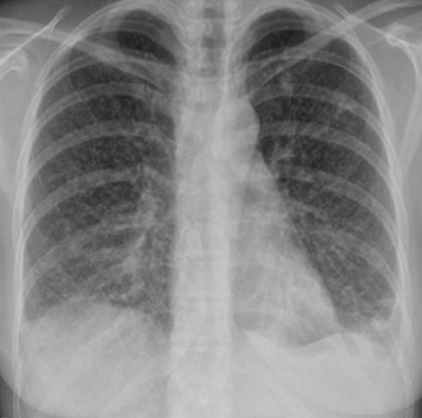

Patient with recurrent attacks of dyspnea and chest tightness after exercise. Clinical diagnosis bronchial asthma. Chest X ray is as follows:

Q1: in this chest x-ray normal or abnormal? Normal.

Q2: on chest auscultation, what added sounds can be heard in asthma? Wheeze.

Q3: Name any drug which can precipitate asthma? NSAIDS, Beta blockers.

Q4: You ordered spirometry for this pt. what will be the expected finding? FEV1 is reduced.

Q5: Name 2 clinical features of severe asthma? Z Can Not complete a sentence in one breath, Tachypnea, cyanosis

Q6: What ttt will you give in moderate to severe asthma? Name any 2. Bronchodilators, corticosteroids.